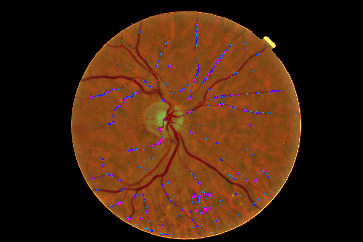

Refer to caption

Figure 4: Pixel probability maps obtained from the final CNN for a different number of epochs. In initial epochs, the probability map include low probabilities of MA (depicted as green spots), in the subsequent epochs, the medium and high probabilities are in blue and purple respectively.